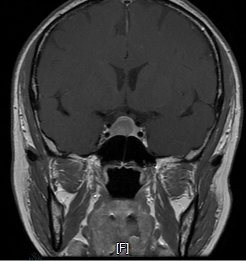

以案解析丨垂體腺瘤合并腦膜瘤處置策略

一位67歲的患者,7年前在體檢中通過MR和CT掃描發(fā)現(xiàn)垂體腺瘤合并額部小腦膜瘤。垂體腺瘤位于鞍內(nèi),無侵襲;額部腦膜瘤表現(xiàn)為明顯骨化。由于當時患者無明確臨床癥狀,因此選擇觀察隨診。近期復(fù)查結(jié)果:患者近期復(fù)查的MR和CT掃描顯示,垂體腺瘤仍位于鞍內(nèi),但比較之前略有增大,不過左側(cè)出現(xiàn)輕微侵襲海綿竇的跡象;額部腦膜瘤大小無明顯變化,骨化情況與前一致,見下【圖1-3】。患者自己感覺身體狀況良好,無明顯不適。處置方案探討:1、繼續(xù)觀察:(1)腦膜瘤:鑒于腦膜瘤在過去7年中未見明顯變化,且表現(xiàn)為骨化病變,無壓迫癥狀,可繼續(xù)觀察隨診。(2)垂體腺瘤:對于垂體腺瘤,盡管出現(xiàn)左側(cè)微侵襲海綿竇的跡象,但患者目前無癥狀,也可選擇定期隨診觀察,密切監(jiān)測病情進展。2、手術(shù)切除(垂體腺瘤):唯一的手術(shù)指征是垂體腺瘤出現(xiàn)侵襲性生長,特別是侵襲海綿竇的情況。如果腫瘤繼續(xù)增大且引起臨床癥狀(如視力下降或激素分泌異常),可考慮手術(shù)干預(yù)。最終決定:經(jīng)過與患者及家屬的充分溝通,考慮到患者的年齡已接近70歲,且目前自覺無任何不適,最終決定繼續(xù)觀察隨診,定期復(fù)查影像和相關(guān)指標。

宗緒毅醫(yī)生的科普號2024年12月05日84